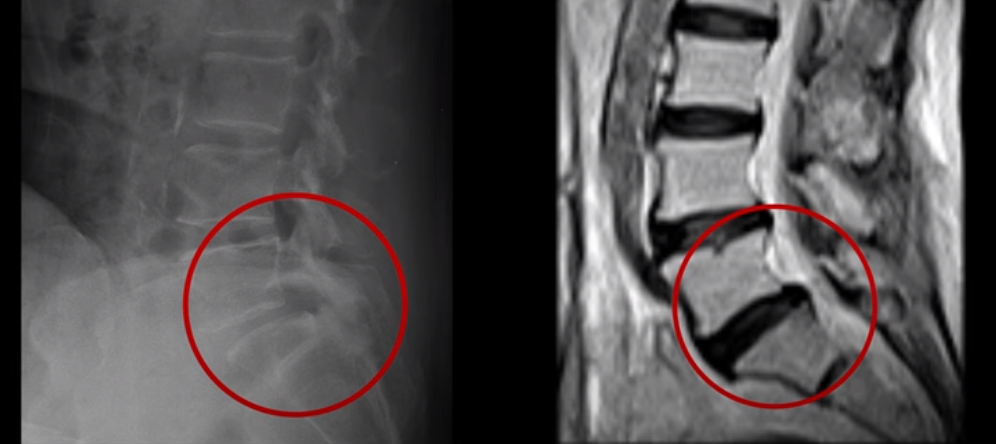

실제 저희 치료후기에 나오는 환자분들의 사례를 들어 설명해드리겠습니다. 이분은 전방전위가 2단계로 매우 심하고,

신경 구멍도 두 마디가 좁아져 있습니다.

전방전위와 협착이 다 심하니까 대학병원에서 나사 6개를 박는 유합술을 권유 받으셨는데요. 그런데 이분이 처음 아프게 된 건 작년 10월인데, 이분이 만약 아프기 전인 작년 초에 MRI를 찍었다면 지금의 MRI와 많이 다를까요? 아닙니다. 거의 차이가 없을 겁니다. 이미 척추 뼈는 많이 밀려나가 있고 신경 구멍은 똑같이 좁아진 상태였을 겁니다. 그 상태로도 전혀 안 아프게 아주 오랫동안 사신 겁니다. 그러다가 작년 10월에 무리한 일과 운동 때문에 허리 근육에 문제가 생기면서 신경이 눌리기 시작한 겁니다. 만일 아프지 않을 때 MRI를 찍고 척추 뼈가 밀려나가고 신경이 눌렸으니까 나사 박는 수술을 하자고 하면, 수술을 받을 사람이 있을까요?